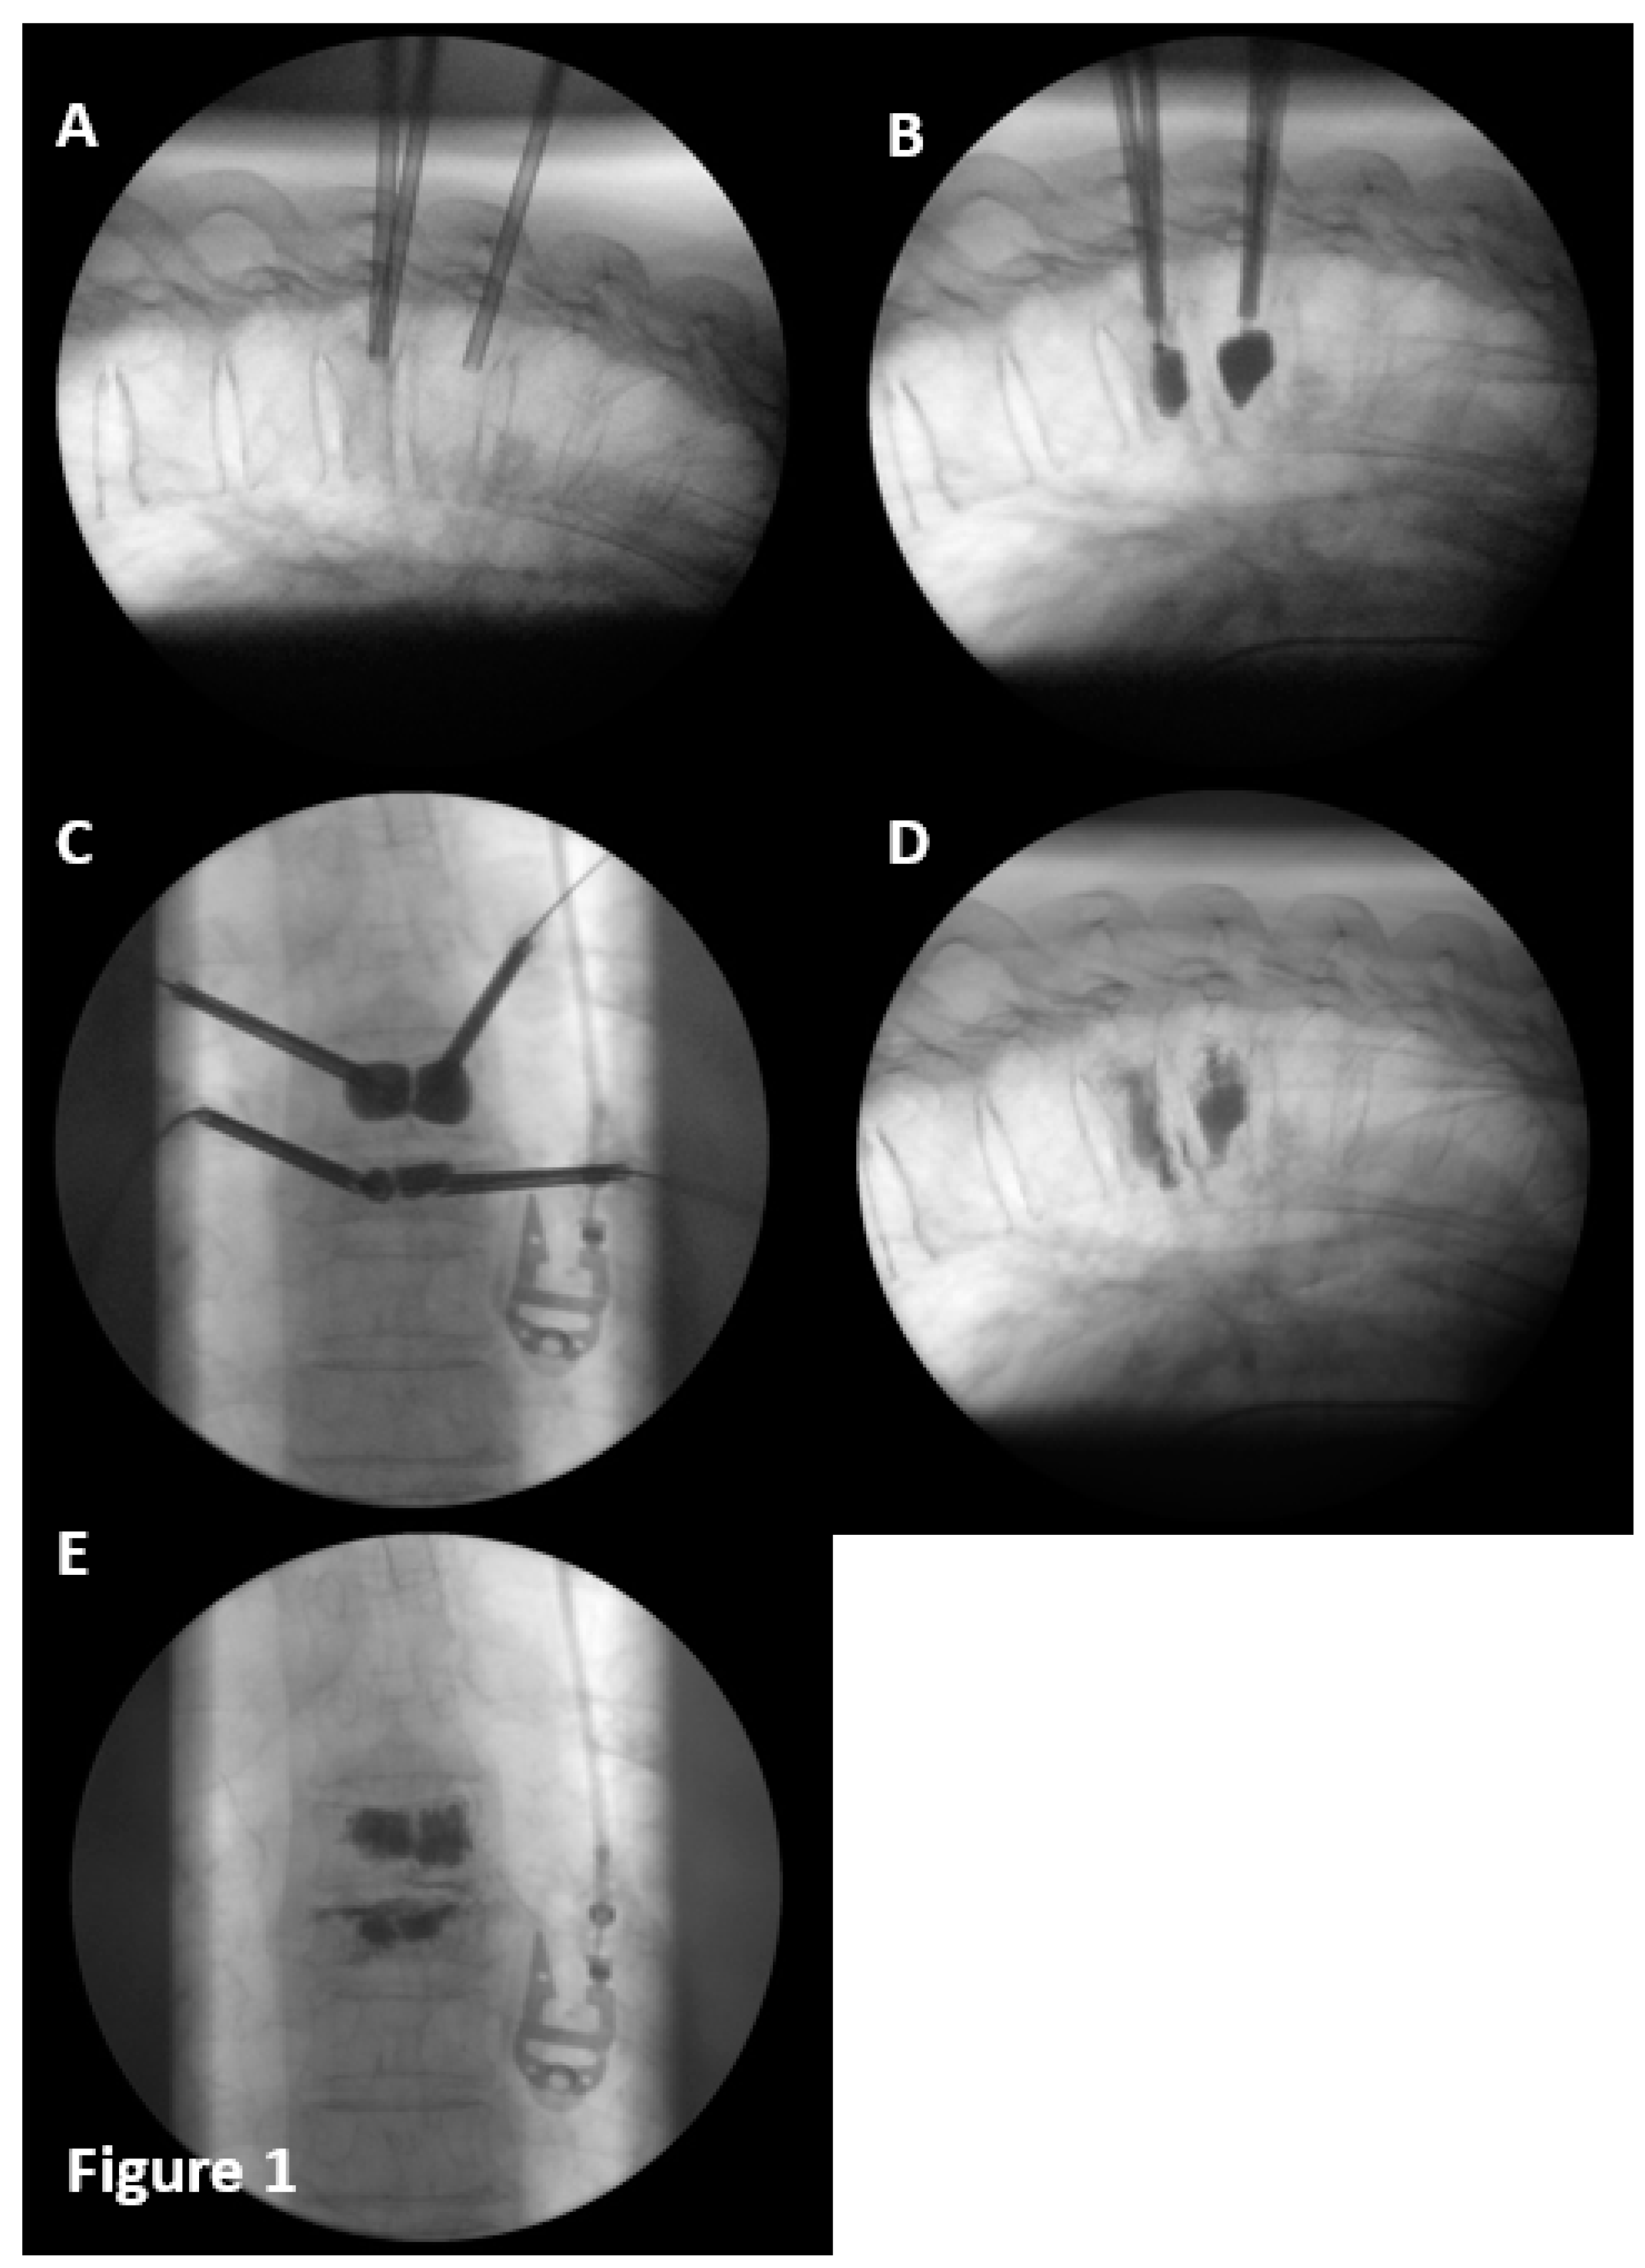

The vertebral reconstruction procedure by balloon kyphoplasty was performed as follows: a simple (Figure 1) or double (Figure 2) 8mm balloon was introduced for each vertebral pedicle.

The balloons were independently and gradually inflated until they reach the desired size, and the bone cement was prepared (BoneOs Inject Bone Cement®). The balloons remained inflated until the cement was ready to be introduced.

Figure 2. Kiphoplasty double balloon procedure. A.-Cannulas with balloons inserted in vertebral body. B.- Fracture in anterior body was reduced by inflating anterior balloons. C.- Fracture in posterior body was reduced by inflating posterior balloons. D.-C in anteroposterior projection. E.- Cemented vertebra in anteroposterior projection. F.-E in lateral projection.